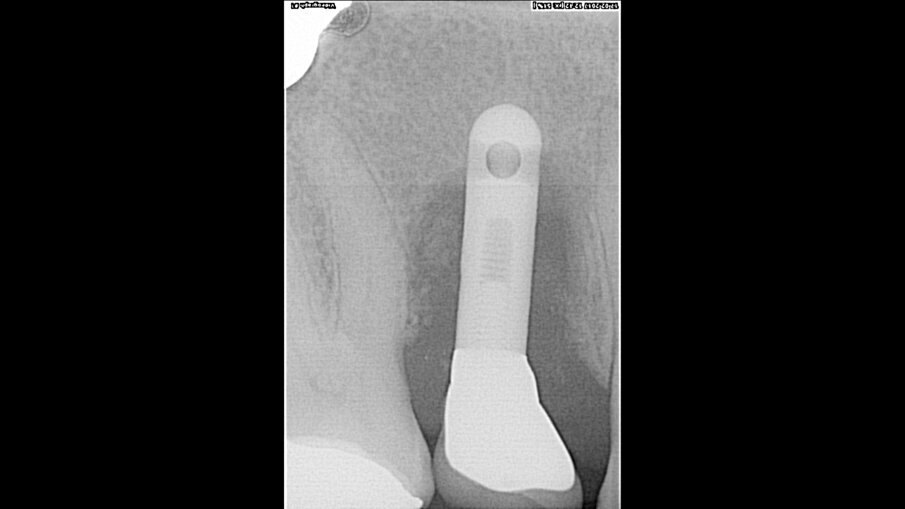

Implantáty byly zaváděny v lokální anestezii (40 mg Dexa­ratiopharm, intramuskulárně; ratiopharm) po premedikaci antibiotiky. Osteotomie byla postupně rozšiřována podle zamýšleného průměru implantátu. Po provedení incize byly odstraněny nekrotické nebo zánětlivé tkáně. Oblasti osteotomie byly preparovány postupnou sekvencí vrtáků podle doporučení výrobce. Implantáty byly zavedeny do oblastí preparované osteotomie za točivého momentu 45 Ncm.

Po chirurgickém zákroku byly pořízeny periapikální RTG snímky, na nichž byla zkontrolována přesnost zavedení implantátů. Pooperační medikace spočívala v předepsání antibiotik. Digitální RTG snímky byly pořízeny v době chirurgického zákroku, po 24 hodinách a jeden měsíc po zákroku, a to za účelem vyhodnocení úspěšnosti implantologického ošetření. Zánětlivé procesy byly zjištěny u 24,1 % pacientů. V případě potřeby byla provedena augmentace za použití materiálu NanoBone (Artoss), kostní náhražky Geistlich Bio­Oss a membrán Geistlich Bio-Gide (oba produkty Geistlich Biomaterials).

Ze 721 implantátů selhalo celkem 65 implantátů. Míra úspěšnosti tedy ve výsledku byla 90,98 %, tedy nižší než v naší předchozí studii provedené u nekuřáků, u nichž byla míra úspěšnosti 98,70 %.2 U skupiny neúspěšných implantátů selhala většina z nich (74,5 %) dva až čtyři týdny po zavedení v důsledku nedostatečné oseointegrace. Periimplantitida se vyskytovala u 20 % neúspěšných implantátů. To lze přičíst špatné ústní hygieně a tvorbě plaku. U 4,6 % případů se periimplantitida objevila v rozmezí jednoho až tří let po zavedení implantátu v důsledku mechanických problémů po úbytku kosti. Nebyla zjištěna žádná souvislost mezi délkou a průměrem implantátu a mírou selhání, ani mezi počtem vykouřených cigaret a mírou selhání implantátu.

Implantologické ošetření je jednoznačnou volbou pro ošetření pacientů s chybějícími zuby. Některé stavy, jako je kouření, hypertenze a diabetes, však mají na úspěšnost dentálních implantátů negativní vliv. Bylo zjištěno, že nikotin způsobuje osteoklastické změny. Na základě zde popsaných případů a výsledků u dalších pacientů lze dojít k závěru, že v současné době je možno dosáhnout dobrých výsledků i u silných kuřáků. Je obtížné vyhodnotit roli jednoho rizikového faktoru, jako je kouření, ve vztahu k dobrým výsledkům implantologického ošetření, protože se u mnoha pacientů vyskytují i další rizikové faktory zahrnující diabetes, pokročilý věk nebo nízkou hustotu kosti. Navíc jsou u kuřáků značné rozdíly, pokud jde o skutečný počet denně vykouřených cigaret a let, po které pacient kouří. Na úspěšnost oseointegrace kromě toho může mít vliv pozice implantátů, a zda jsou zavedeny v horní nebo dolní čelisti. U kuřáků totiž dochází k většímu úbytku okrajové kosti kolem implantátů v horní čelisti. Příčina selhání implantátu se tedy může lišit i s ohledem na umístění implantátu v souvislosti s kvalitou a množstvím alveolární kosti, do které je implantát zaveden. Každá alveolární kost se také liší z hlediska minerální hustoty, mikrostruktury a tloušťky trabekulární kosti.